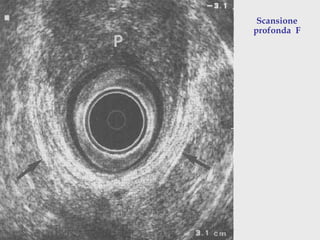

A: tessuto subepiteliale

B : sfintere anale interno

C: muscolo longitudinale

D : sfintere esterno

Scansione

profonda F